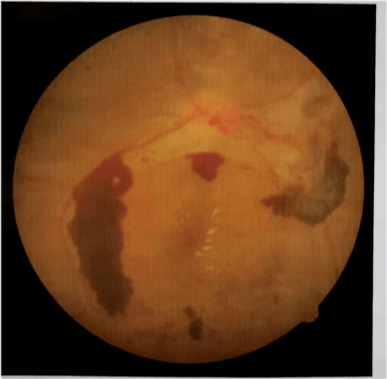

发生眼底病变的糖尿病患者会出现一系列的眼部症状表现 , 比如玻璃体积血导致的帷幕样遮挡、玻璃体积血消退过程中的飞蚊症 。

发展到最后还有可能引起新生血管性青光眼 , 它除了可以导致患者视力下降、失明外 , 还会引起持续的眼痛、头痛、恶心、呕吐等 , 患者将承受巨大的痛苦 。

病程在10年左右的患者视网膜病变率达到了50% , 15年以上更是达到了80%!